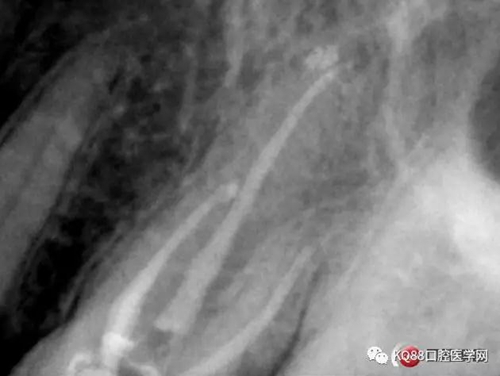

Y形態(tài)變形成了,根間支也明顯出現(xiàn),充填嚴密,雖然根管治療的成功率不是一百,但是我們盡可能把那一點做到位,往往結(jié)果可能會很驚人,如果我在第一次就充填了,可能也不會有什么錯誤,但是態(tài)度就已經(jīng)輸了,我們基層做根管不會像武大等那么規(guī)范,但是也希望可以向其靠攏,一個好的根管,上面才能有美的修復。

四個根管成型,只是近中兩個根管融合為一個,典型的C型根管。最后開始根充,射片。

充填完成。以此兩例根管治療,說明的并不是完全技巧,更多的是態(tài)度,我的根管治療做的并不是很好,但是我一定會把態(tài)度端正起來,希望同行們都能一起加油,利用手上最基本的設備,用心做好每一個根管。如有錯誤,請多指證,謝謝!